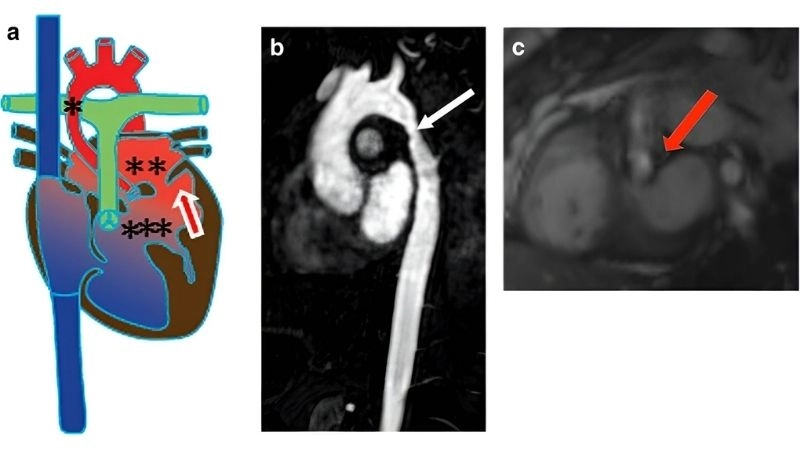

Images visual examples of Shone's Complex

Shone's Complex is a rare congenital heart defect affecting the left side of the heart, often involving multiple obstructive lesions that impair normal blood flow.